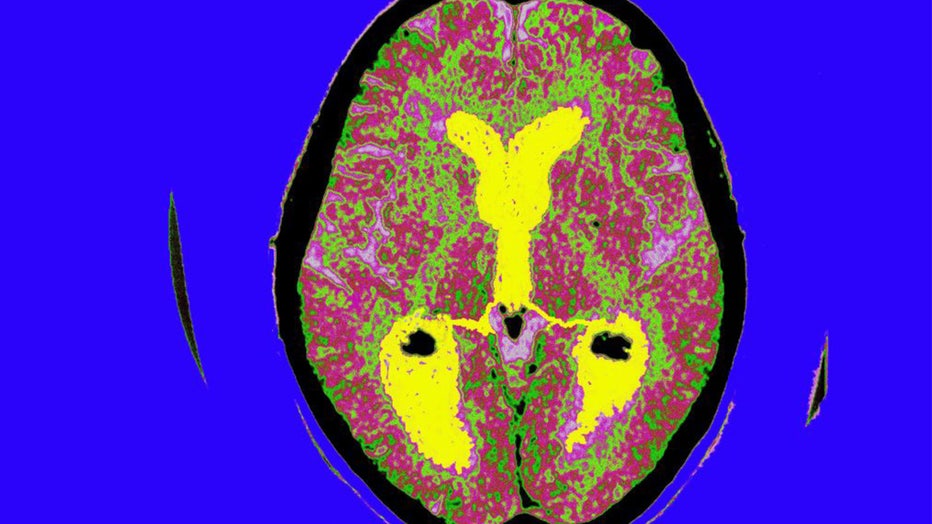

0ea2ad47-Alzheimers.jpg

FILE - Alzheimer's Disease, Scan, Brain Of A Patient Affected By Alzheimer's Disease, Axial Section, Median Portion Of Dilated Third Ventricle, Symmetrical Dilation Of Intersections, Whereas The Cortical Horns Are Normal In Size.  (BSIP/Universal Images Group via Getty Images)